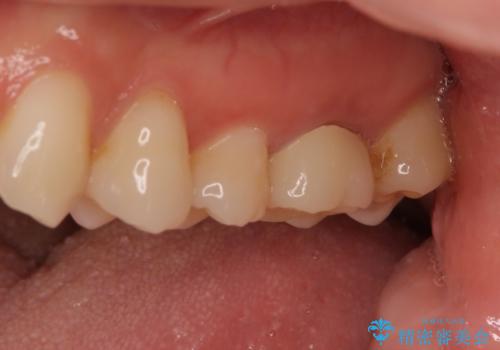

海外転勤が決まり、急いでセラミック治療をしてほしいとご来院された患者様です。

根管治療に症状がなく、上の歯に関しては土台もそのまま使用可能であったため、下の歯の土台、上下の歯のセラミック治療を行いました。

今回は幸い、症状がなく、根管治療の再治療が必要でないため、円滑に治療を進めることができました。